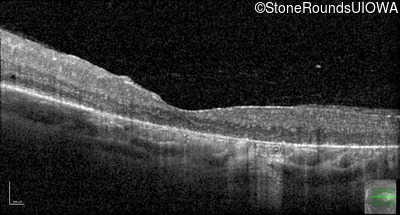

Optical Coherence Tomography - Right - 20/160

Exemplar / OCT Stack

OCT Stack